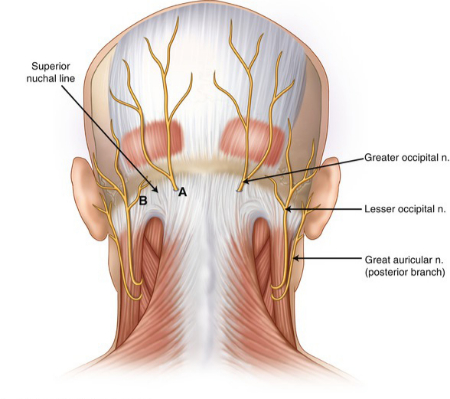

درد در پشت سر معمولاً جای نگرانی ندارد، جز اینکه چگونه بر فعالیتهای روزمره شما تأثیر میگذارد. درد در پشت سر اغلب ناشی از انواع مختلف سردرد مانند سردرد تنشی، میگرن یا سردرد ناشی از فعالیت بدنی است. با این حال، در برخی موارد، درد در پشت سر میتواند نشاندهنده نوع جدیتری از سردرد باشد، مانند سردرد با فشار کم یا سردرد سرویکوژنیک (ناشی از مشکلات گردنی). این درد همچنین ممکن است نشانهای از یک وضعیت عصبی مانند نورالژی اکسیپیتال باشد که به دردهای مرتبط با اعصاب اشاره دارد.

درد پشت سر معمولاً نیازی به توجه پزشکی ندارد. این درد معمولاً ناشی از سردرد تنشی یا میگرن است، وضعیتهایی که میتوان آنها را با درمانهای خانگی، داروهای بدون نسخه یا تغییرات سبک زندگی درمان کرد. گاهی اوقات درد پشت سر میتواند نشانهای از یک مشکل جدیتر مانند نورالژی اکسیپیتال یا سردرد با فشار کم باشد که نیاز به مداخله پزشکی دارد.

• نورالژی اکسیپیتال: این وضعیت میتواند با داروهایی مانند شلکنندههای عضلانی، ضدتشنجها یا ضد التهابها درمان شود. درمانهای غیر دارویی شامل فیزیوتراپی و پدهای گرم است. همچنین، نورالژی اکسیپیتال میتواند با جراحی درمان شود. جراحی برای درمان نورالژی اکسیپیتال شامل تحریک اعصاب گردن برای مسدود کردن سیگنالهای درد است.